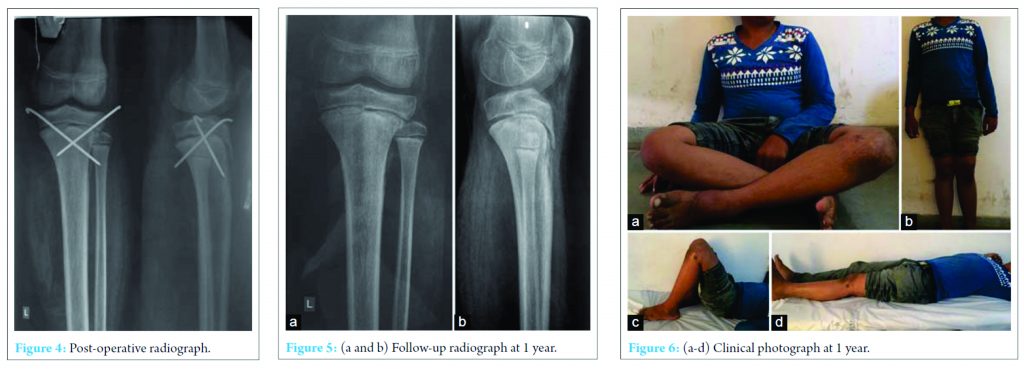

Two cross K-wires were inserted percutaneous from lateral and medial side and though mini-open approach from proximal epiphysis to metaphysis. The reduction was found to be stable enough, and proximal fibular epiphysis was also stable, distal pulses were felt post reduction, Above knee posterior and anterior slab was given in 15° knee flexion to avoid popliteal vessel compression (Fig. 4).

Post-operative patient was immobilized with nil weight bearing for 4 weeks, check X-rays taken, he was mobilized in wheelchair. After 4 weeks slab was removed, K-wires were removed and partial weight bearing was started with rehabilitation for full range of motion of the left knee. At 6 weeks both the knee joints appeared symmetrical with no abnormalities or limb length discrepancy or instability with knee from 0° to 140°, with full weight bearing (Fig. 5a and b, 6a).

Follow-up at 1 year showed the full range of motion, no joint laxity, and no limb length discrepancy (Fig. 6b-d).